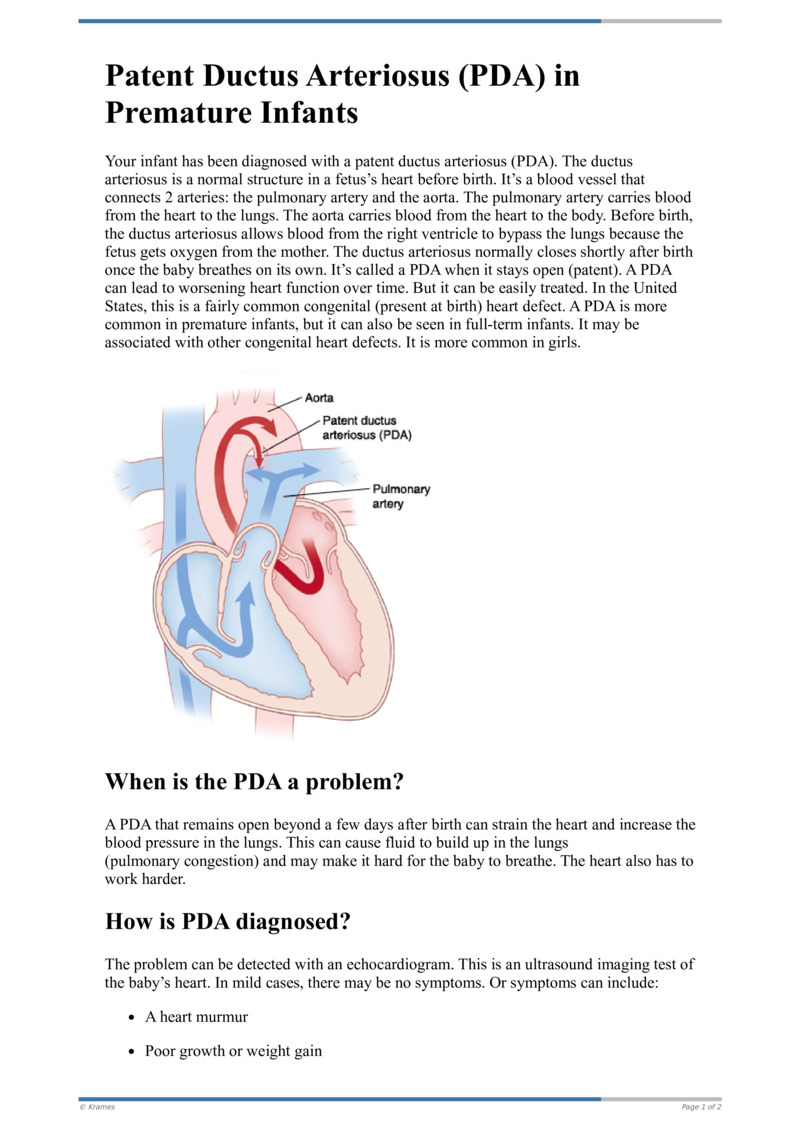

PDA Pathophysiology and Anatomy

Morphology of the PDA in premature infants The PDA resembles a hockey

Text Patent Ductus Arteriosus PDA in Premature Infants

PATENT DUCTUS ARTERIOSUS PDA IN CHILDREN Dr Gaurav Agrawal

Patent Ductus Arteriosus PDA in the newborn